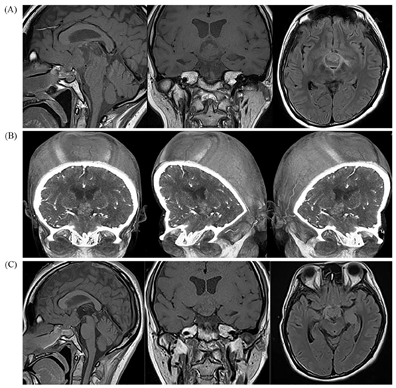

患者女性,22岁,因"头痛伴停经1年余,发现血糖升高7个月"之主诉于2018年1月入住本科。1年前因"头痛伴停经"诊断为"颅咽管瘤",10个月前在国外医院检查,晨8∶00血皮质醇14.0 μg/dl(参考范围5.0~28.0 μg/dl,下同)、促甲状腺激素(TSH)2.62 μIU/ml(0.5~4.5 μIU/ml)、FT4 0.9 ng/dl(0.8~1.8 ng/dl),行头颅磁共振(MRI)三维重建检查,诊断为"颅咽管瘤",行"经鼻蝶窦肿瘤切除术"联合"头颅穿孔减压术+去除肿瘤囊性部分"治疗,手术病理示:"乳头型颅咽管瘤(BRAF V600E突变阳性)",术后出现腺垂体功能减退、视野缺损及尿崩症等一系列相关并发症,分别给予"氢化可的松、左甲状腺素钠、去氨加压素"等药物治疗,临床症状好转(图1)。8个月前再次因"头痛"在另一国外医院诊断为"脑积水",给予"脑室腹腔分流置管术"治疗(图2)。7个月前出现精神差、偶有幻觉、短时记忆受损,复查发现"颅内肿瘤增大",于国外当地医院行放射治疗30次(放疗累积总剂量为54 Gy),为防治"脑水肿"给予口服"地塞米松4~8 mg/d"2月余,逐渐出现食欲增大、血糖增高,多次监测空腹血糖>8 mmol/L(3.9~6.1 mmol/L),伴体重增加、嗜睡、少动,未予药物治疗。4个月前再次复查"颅内肿瘤体积增大",于国外医院行"开颅肿瘤切除术"(图3),术后停用"地塞米松",改为"泼尼松40 mg/d"治疗,逐渐减量;治疗过程中逐渐出现肥胖,体重共增加约50 kg,腹部及四肢皮肤出现宽大紫纹,监测血糖升高,空腹血糖最高达15~16 mmol/L,自服"二甲双胍1.0 g/d",未规范治疗。

注:(A)术前核磁共振成像(MRI);(B)术前MRI三维重建;(C)术后MRI

本病例有典型的颅咽管瘤的症状和影像学表现,术前头颅CT和MRI表现为鞍区以实性为主的囊实性中心病灶,诊断为"颅咽管瘤",经历了第1次手术治疗(图1),手术方式选择了"经鼻蝶窦肿瘤切除术"加"头颅穿孔减压术",主要的目的是为了尽可能地保护下丘脑、垂体和视交叉等重要结构功能,然而术后复查发现鞍区肿瘤未完全清除(图1C)。术后3个月"颅咽管瘤复发",行放射治疗;术后半年再次复查"颅内肿瘤体积增大",进行第2次手术治疗,手术方式选择了"开颅肿瘤切除术"(图3)。临床医生需根据肿瘤的位置、大小、生长方式以及与周围结构的毗邻关系等综合评估,以选择手术方式[3,4]。